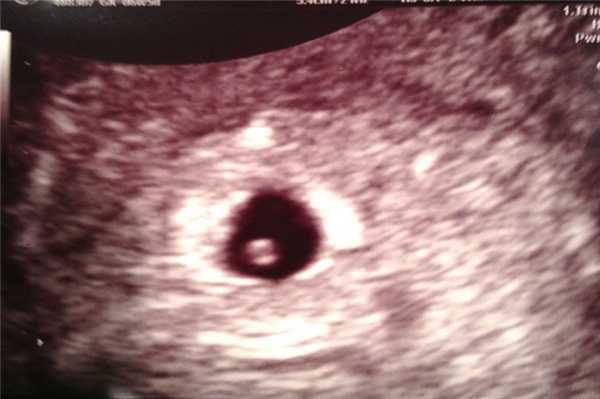

Фото УЗИ ребенка на 10 неделе беременности

На десятой акушерской неделе завершается закладка крупных внутренних органов. Вес малыша составляет уже 5 грамм. Хрящевая ткань при этом начинает уплотняться, превращаясь в костные структуры.

На фото УЗИ уже хорошо видны ручки и ножки малыша. Его голова несоизмеримо больше остального тела, а лобная часть явно выступает вперед. Пугаться этой особенности не стоит - это норма. Также на снимке можно отчетливо различить губы, нос и уши. Проводя ультразвуковое исследование, врач прослушивает сердцебиение, видит первые слабые движения конечностей. Также специалист может осмотреть строение позвоночника.

Фото УЗИ ребенка на 11 неделе беременности

На этом сроке малыш увеличивается до 45-60 мм, что позволяет отчетливо видеть его на снимке УЗИ. Его сердцебиение лежит в пределах 120-160 ударов в минуту. Происходит формирование дыхательной системы.

На фото видны такие изменения плода:

- руки малыша, длиннее ног, а размеры головы сопоставимы по размерам со всем остальным телом;

- у плода формируется шея, что позволяет ему совершать движения головой;

- между пальцами пропадают перепонки, ребенок пытается сжимать их в кулачки и разжимать;

- в связи с полным отсутствием жировой ткани, на УЗИ видны сосуды, просвечивающиеся через кожу;

- шевеления плода еще слабые, но они видны на экране прибора;

- начинается формирование гениталий.